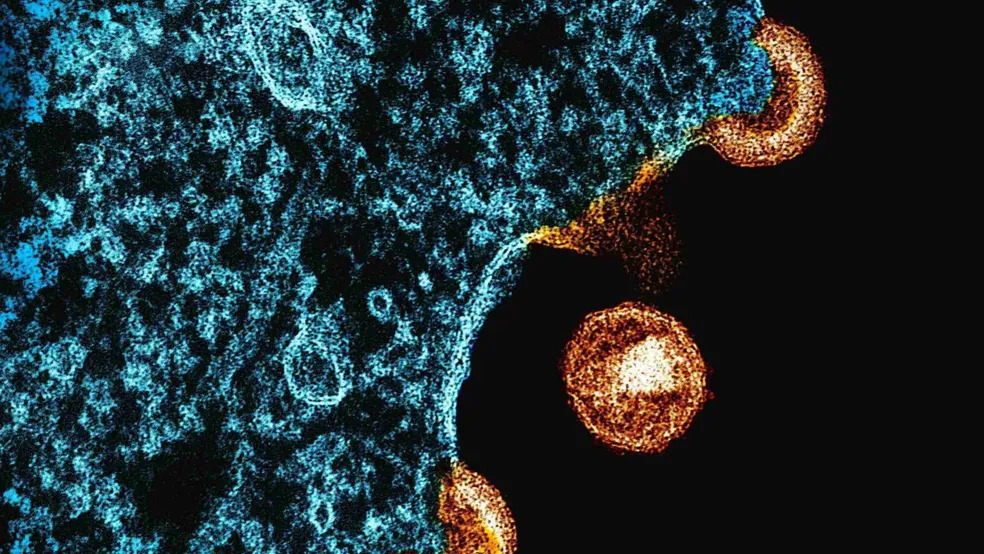

Destaque OMS reconhece fim de transmissão do HIV de mãe para filho no Brasil Ler Mais » jornaldepaulinia 15 de dezembro de 2025